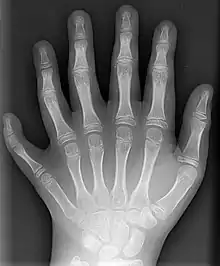

Static adult human physical characteristics of the hand

X-ray showing joints- Hand bone anatomy